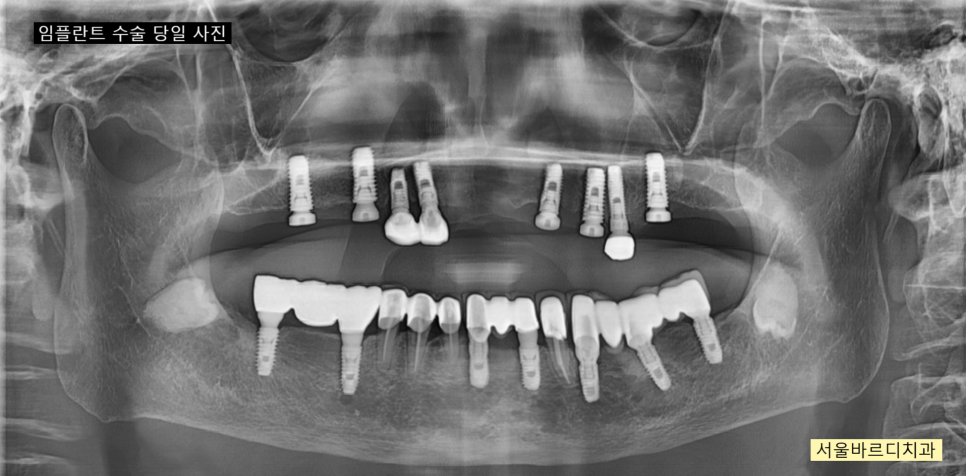

수술은 네비게이션 임플란트 방식으로

한번에 진행되었고

250305

치료 과정에서

기존에 심겨진 임플란트는 최대한 활용하였습니다.